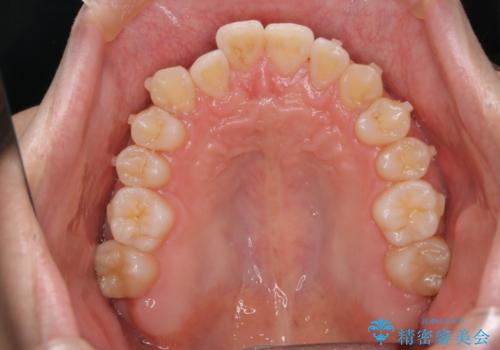

- 前歯のがたつきを主訴に来院されました。初診時、右上2番の口蓋側転位と右下7番の舌側傾斜が認められました。

インビザラインにてIPRと歯列弓拡大を行い、ゴム掛けで噛み合わせを改善する治療計画を立てました。

マウスピースの使用時間が短いため、シュミレーション通り進むか不安でしたが

治療期間1年で、主訴である前歯のがたつきを改善出来、

奥歯の噛み合わせも良くなりました。